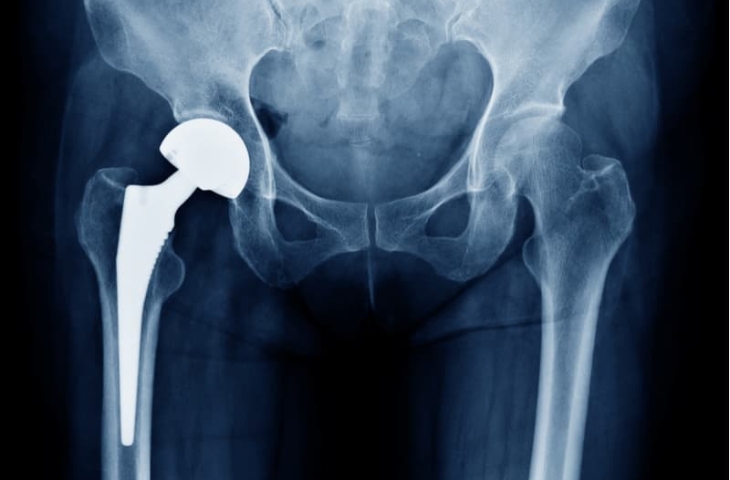

Phẫu thuật thay khớp háng toàn phần là kỹ thuật thay toàn bộ bề mặt khớp hư hại của xương đùi và ổ cối bên khớp háng bị tổn thương, thường áp dụng với các trường hợp thoái hóa, hoại tử chỏm xương đùi giai đoạn nặng… Phương pháp này đòi hỏi bệnh nhân có sức khỏe tốt, kiểm soát được bệnh lý nền để trải qua cuộc mổ kéo dài.

thay khớp háng toàn phần Thay khớp háng toàn phần là loại bỏ toàn bộ bề mặt khớp hư hại của xương đùi và ổ cối.